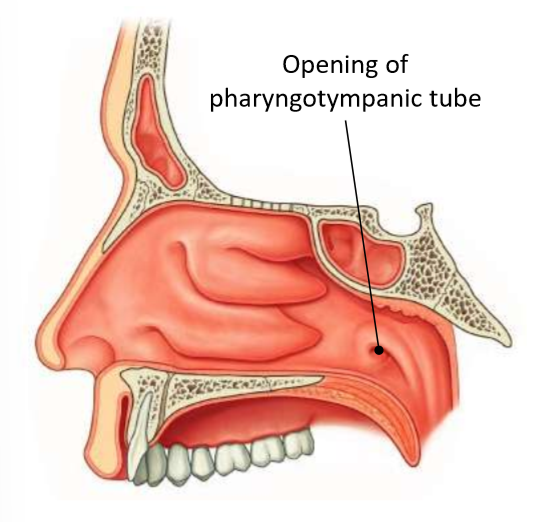

What is 1?

pharyngeal tonsil

What is 2?

pharyngeal opening of pharyngotympanic tube

What is 3?

tubal elevation

What is 4?

salpingopharyngeal fold

What is 5?

tubal tonsil

What does the pharyngotympanic tube connect?

middle ear and nasopharynx

What does the pharyngotympanic tube do?

equalises pressure on each side of the tympanic membrane

What are the two parts of the pharyngotympanic tube?

bony third near the middle ear, rest is cartilaginous